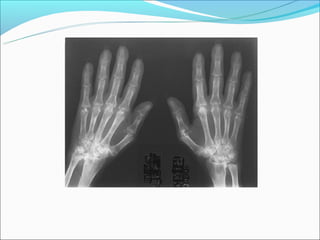

Artrite Reumatóide

Doença do tecido conjuntivo de etilogia

desconhecida.

Pode acometer qualquer articulação sinovial do

corpo.

Edema de Tecidos Moles

Osteoporose

Estreitamento do espaço articular

Erosões marginais